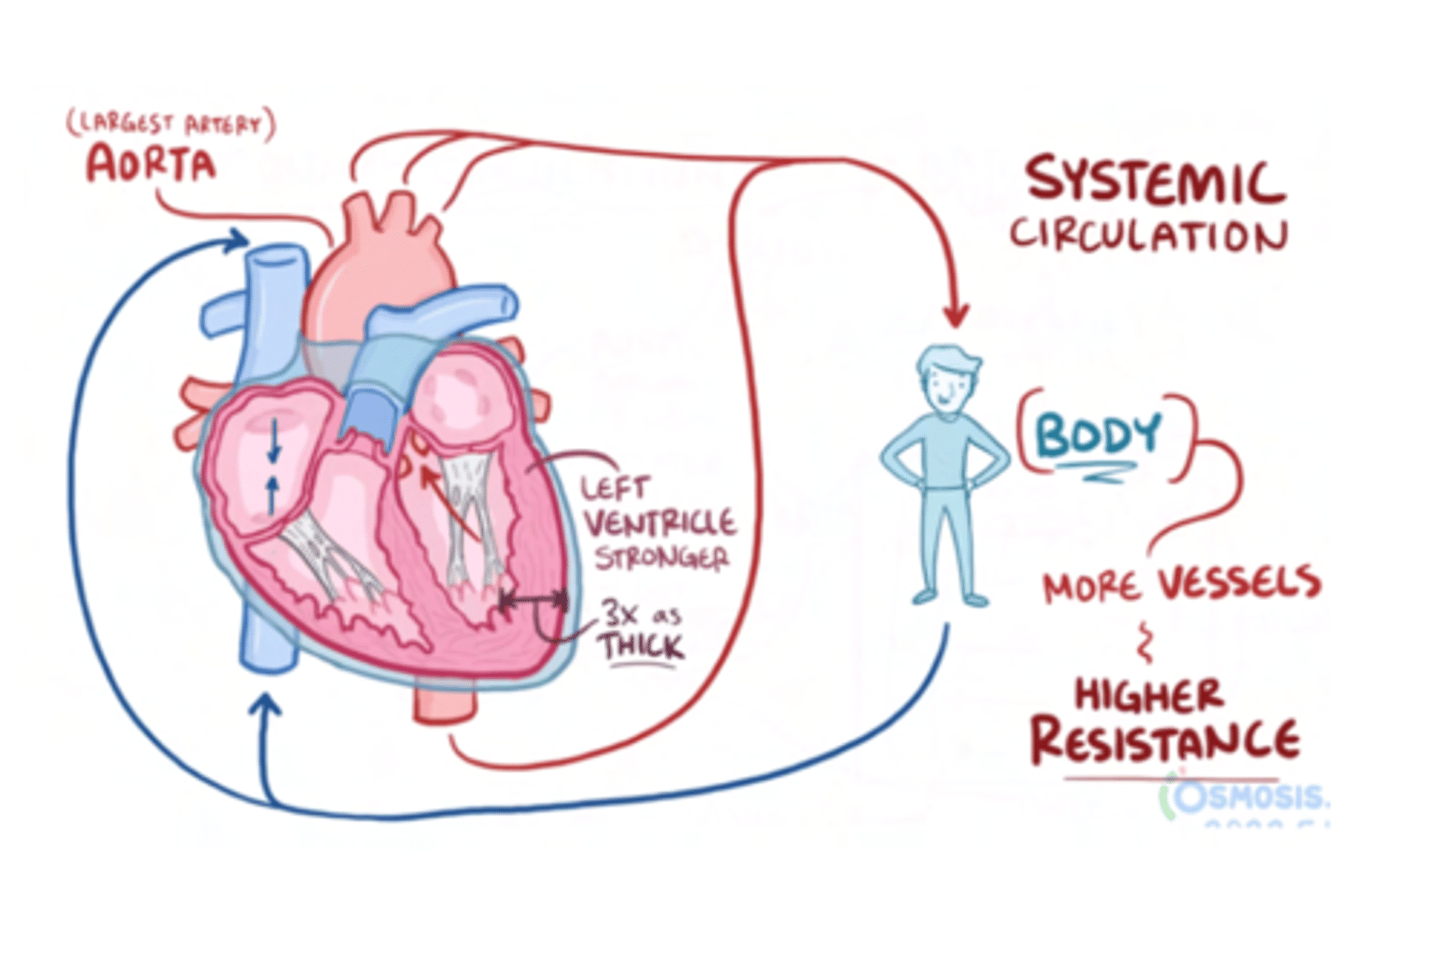

Why is the left ventricle wall thicker than the right?

It is 3 times thicker than the one on the right, in order to pump blood into the aorta at high pressures

SAME THICKNESS AT BIRTH, IT IS DEVELOPED DUE TO THE HIGH PRESSURE OF THIS CAVITY

SYSTEMIC CIRCULATION

flow of blood from body tissue to the heart and then from the heart back to body tissues

It carries oxygen and nutrients to the cells and picks up carbon dioxide and waste products

Describe in detail systemic circulation

From the left ventricle, oxygenated blood,

through the arteries,

to the capillaries in the tissues of the body.

From the tissue capillaries, the deoxygenated blood

returns through a system of veins to the right atrium of the heart. (superior and inferior cava veins)